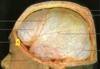

Which arteries do the arrows point to? [1]

Lenticulostiate arteries